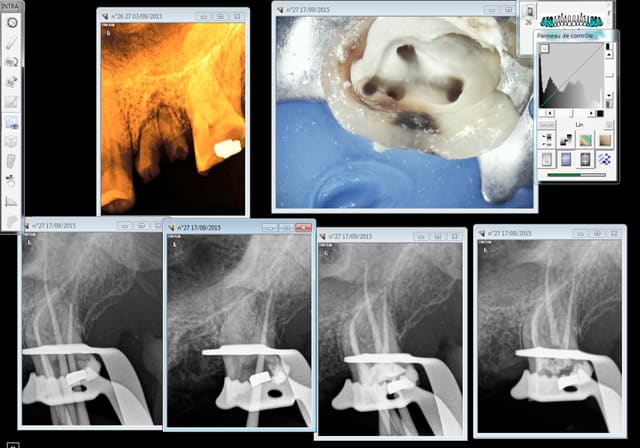

Capture d e cran 2015 09 17 20.25 - Eugenol